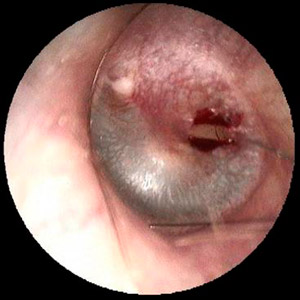

Loch im Trommelfell eines Hobbygärtners durch Stich mit einer Yucca-palme

Loch im Trommelfell nach Schienung mit Silikon